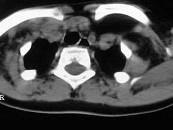

问题 女,17岁,发现左侧颈部包块半年余,PE:病灶质软,境界不清,无压痛,CT如图所示,应诊断为()

选项 A.颈部脂肪瘤 B.颈部畸胎瘤 C.颈部错构瘤 D.颈部淋巴管瘤 E.颈部陈旧性血肿

答案 A